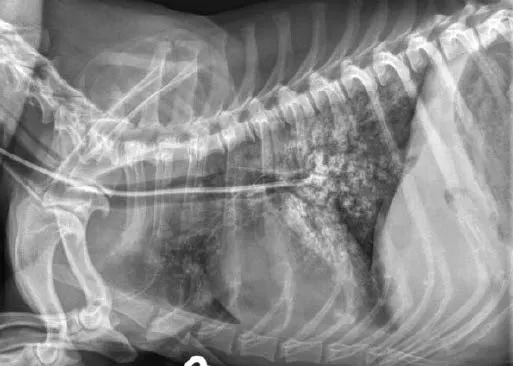

Tubes can be accidentally misplaced in the trachea (Figure 2A), nasopharynx, or nasal cavity, and subsequent feeding may result in aspiration pneumonia; therefore, appropriate placement should be confirmed before feeding is initiated. Various inexpensive methods can help verify tube location: laryngoscopic visualization of the tube entering the esophagus; suction to verify negative pressure; air infusion while auscultating the abdomen for borborygmus; infusion of sterile saline or nonionic contrast medium (Figure 2B), which sometimes elicits a cough with tracheal placement; or pH assessment of fluid aspirated from the tube.

Inadvertent placement of an NG tube in the trachea and bronchus of a miniature dachshund (11 years of age). This dog had a severe pulmonary interstitial pattern secondary to infusion of 20 mL of sterile saline through the tube; it had no cough reflex during infusion (A). After injection of 3 mL of iohexol 240, positive contrast medium outlined the alveoli, particularly in the caudodorsal thorax, confirming tube misplacement (B). The following day, radiography confirmed that contrast medium and saline had been cleared from the lungs.